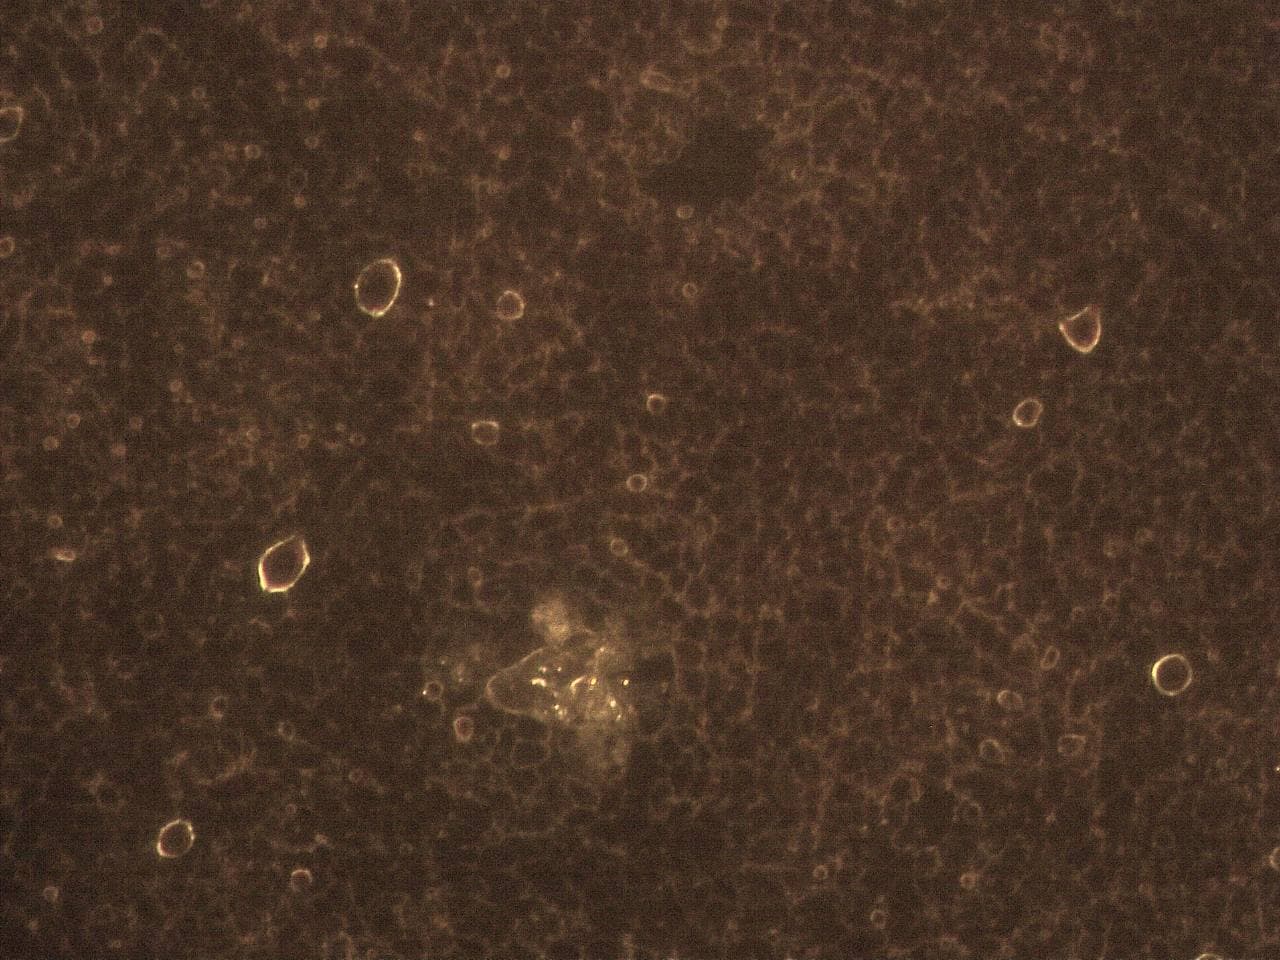

GENimpfschaden

Impfschäden Schweiz

GENimpfschaden

Impfschäden Schweiz Coronaimpfung, [15.09.21

https://t.me/Impfschaden_Corona_Schweiz/21522

Scheibenartiges Gebilde mit leuchtenden Punkten

GENimpfschadne im Blutbild 15.9.2021: Foto 1